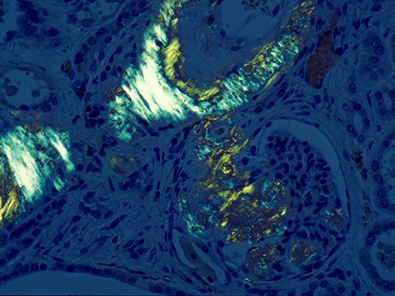

a.腎アミロイドーシス(コンゴ赤染色で橙赤色),b.同染色の偏光観察,c.2型糖尿病患者の膵ランゲルハンス島にみられたアミロイド沈着

67歳,男性.肺結核が疑われて病変部の生検検査がおこなわれた.HE染色標本(1)と同一組織のコンゴ赤染色(2)の組織像である.正しいのはどれか.

2. コンゴ赤染色

正解:d